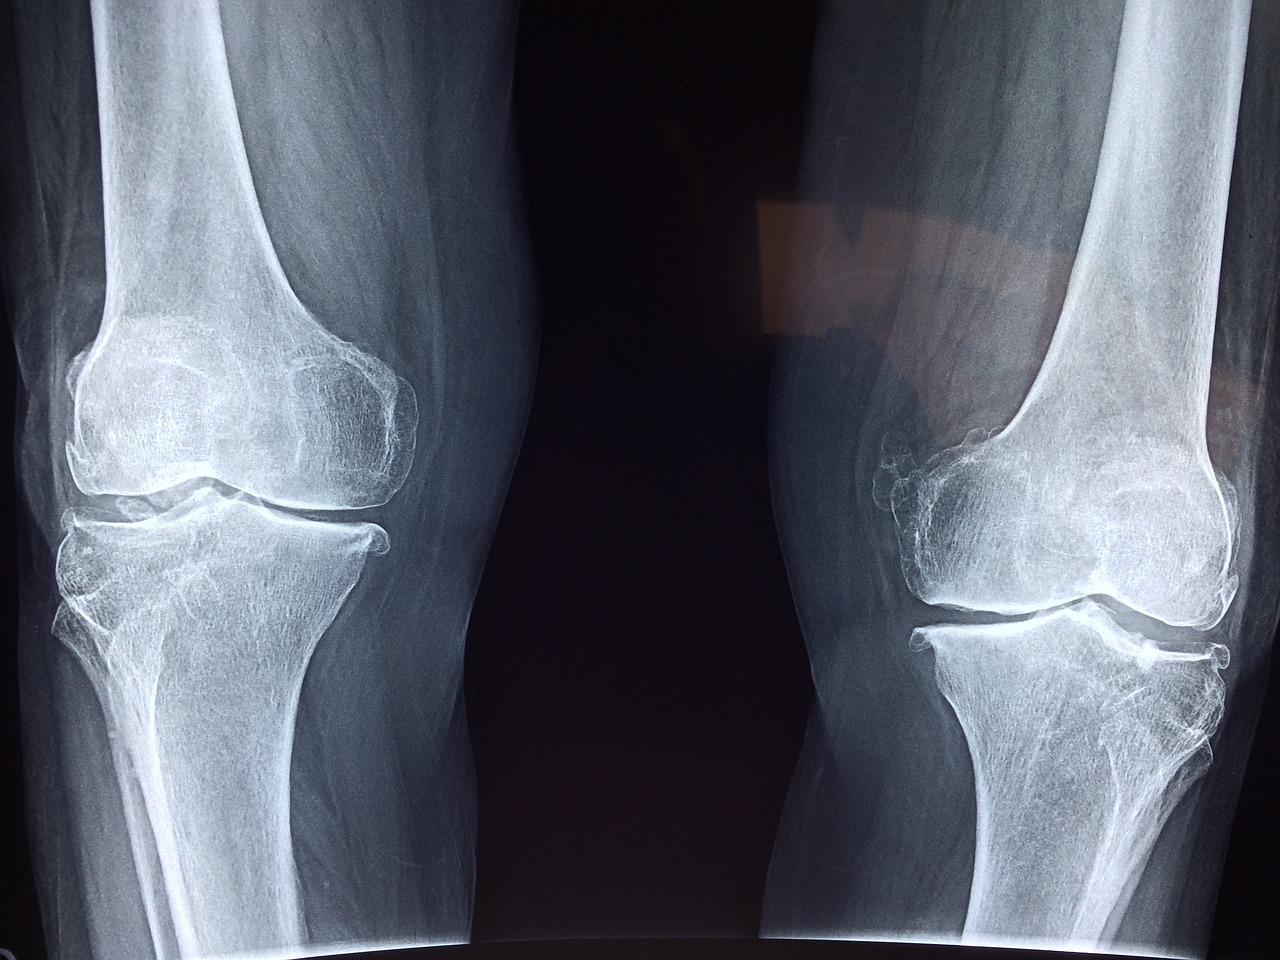

골다공증은 골밀도와 질의 감소로 인해 뼈가 약해지고 부서지기 쉬워 골절되기 쉬운 만성 질환입니다. 그리스어에서 파생된 용어 자체는 "다공성 뼈"로 번역되며, 이 상태의 영향을 받는 뼈의 다공성 특성을 강조합니다. 골다공증은 노화와 관련이 있는 경우가 많지만 연령과 성별에 관계없이 개인에게 영향을 미칠 수 있으며 특히 폐경 후 여성이 취약합니다. 골다공증의 핵심에는 자연적인 뼈 재형성 과정의 불균형이 있습니다. 우리의 뼈는 오래된 뼈 조직이 분해되고(흡수) 새로운 뼈 조직이 형성(형성)되는 재생 주기를 지속적으로 겪습니다. 골다공증에서는 새로운 뼈의 생성이 오래된 뼈의 제거 속도를 따라가지 못하여 뼈 질량의 순 손실과 구조적 완전성 손상을 초래합니다. 이러한 불균형은 연령, 호르몬 변화, 영양 결핍 등 다양한 요인의 영향을 받습니다.

골절: 골다공증성 골절은 이 질환의 특징입니다. 골절은 최소한의 힘이나 외상으로도 발생하는 경우가 많으며 이동성과 삶의 질에 영향을 미치는 심각한 결과를 초래할 수 있습니다.